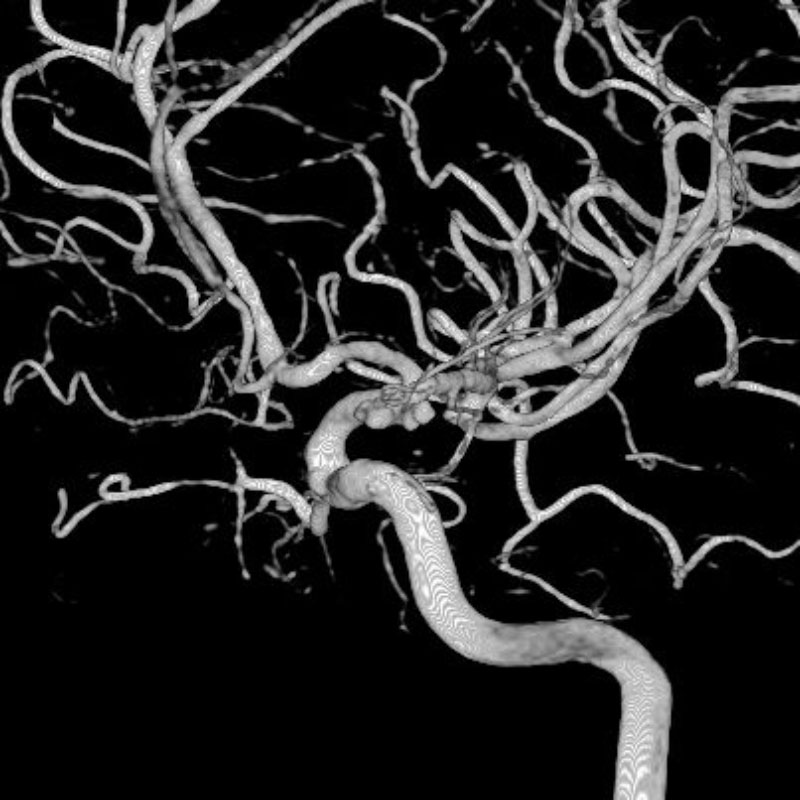

脳動脈瘤(Rt.IC)

フローダイバーター留置術

松田/濵田/元永